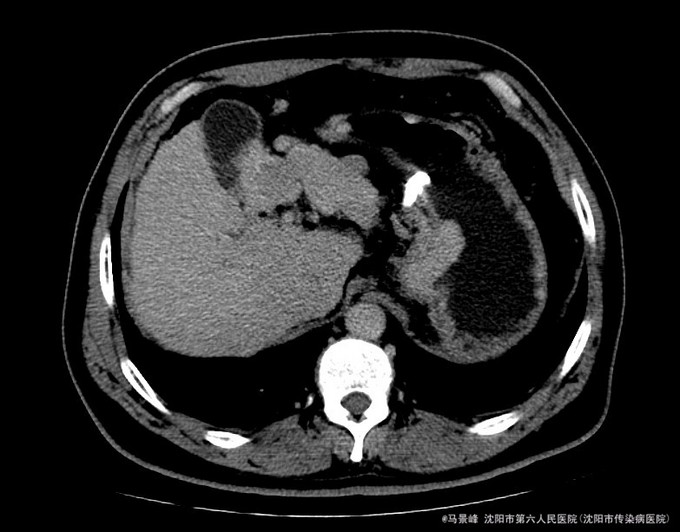

患者术后自觉无明显不适,食欲睡眠可,尿便正常。查体:巩膜无黄染,心肺听诊无异常,腹软,无压痛,肝肋下未触及,移动性浊音阴性,双下肢无浮肿。TACE术后一周,复查CT和肝功ALP和GGT轻度升高,CT示病灶碘油沉积增加,办理出院。出院后继续抗病毒治疗,嘱其2个月后复查。